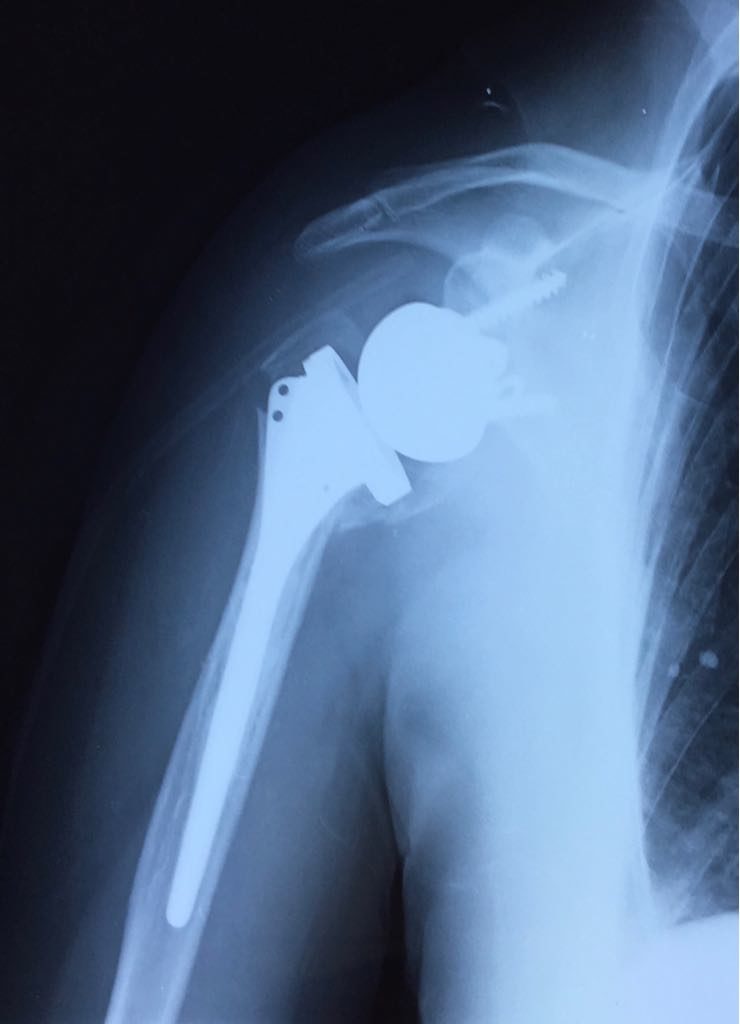

Cliquer sur une photo pour défiler la collectionFracture proximale de l ‘humérus à 4 fragments, femme âgée 78 ans

Prothèse épaule inversée avec réinsertion des tubérosités